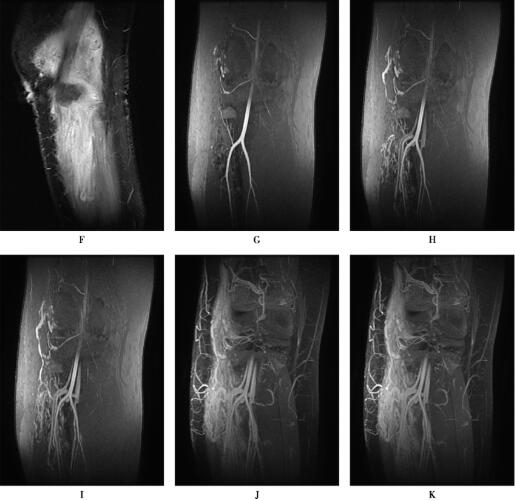

图1 下肢软组织内血管瘤

CE-MRA显示粗大的供血动脉、畸形血管团和迂曲扩张的引流静脉,皮下脂肪内可见曲张静脉。

DSA经皮超选择性动脉造影:右膝、胫骨外侧动脉期可见增粗胫前动脉分支供血,动脉中末期上述部位可见畸形血管团,引流静脉进入腘、股静脉,证实为动静脉畸形,向畸形血管团内注入1.5ml无水酒精+0.5mPVA+博来霉素混合液行畸形血管栓塞治疗。